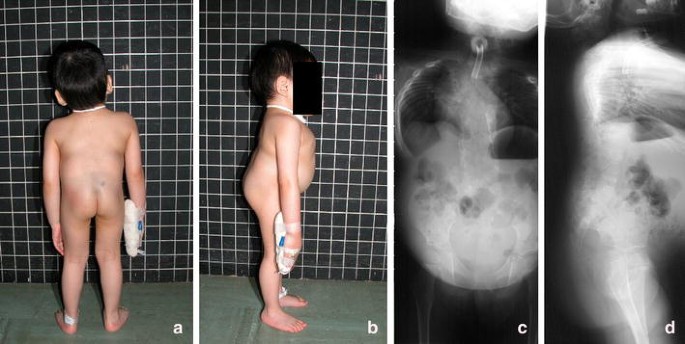

Jarcho–Levin Syndrome is a rare genetic disorder that affects the development of the spine and ribs, leading to a short trunk, short neck, and abnormal curvature of the spine. It is a type of short-trunk dwarfism that can severely affect breathing and physical development due to a small chest cavity. The condition appears at birth or in early infancy and can vary in severity.

- Abnormal curvature of the spine (scoliosis, kyphosis)

- Irregularly shaped or fused vertebrae

- Small chest cavity leading to restricted lung growth

- Abnormal rib alignment, spacing, or fusion

- X-rays or MRI scans to evaluate spine and rib anomalies